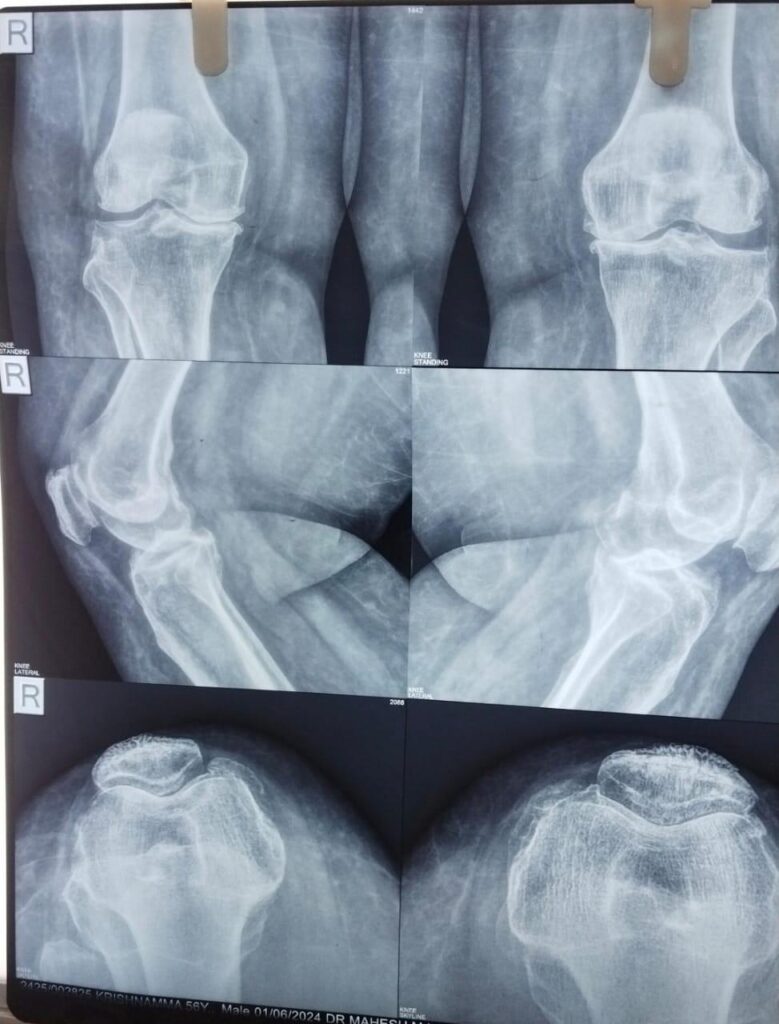

Knee pain can be a debilitating condition, especially when it limits one’s ability to perform everyday activities. For Smt. Krishnamma, a 60-year-old resident of Andhra Pradesh, the last five years had been a challenging journey. Struggling with severe osteoarthritis in both knees, she was unable to walk properly, and her quality of life had significantly declined.

Osteoarthritis is a common condition among older adults that causes joint pain and stiffness due to the gradual wearing down of cartilage. For Smt. Krishnamma, it led to unbearable pain and restricted her mobility, making even simple tasks seem insurmountable.

Determined to find a solution, she sought care at Sathya Sai Orthopaedic & Multispeciality Hospital, where she consulted Dr. Mahesh MN, a renowned orthopaedic and joint replacement surgeon. After a thorough evaluation, Dr. Mahesh diagnosed her with severe osteoarthritis of both knees and recommended total knee replacement surgery for both knees.